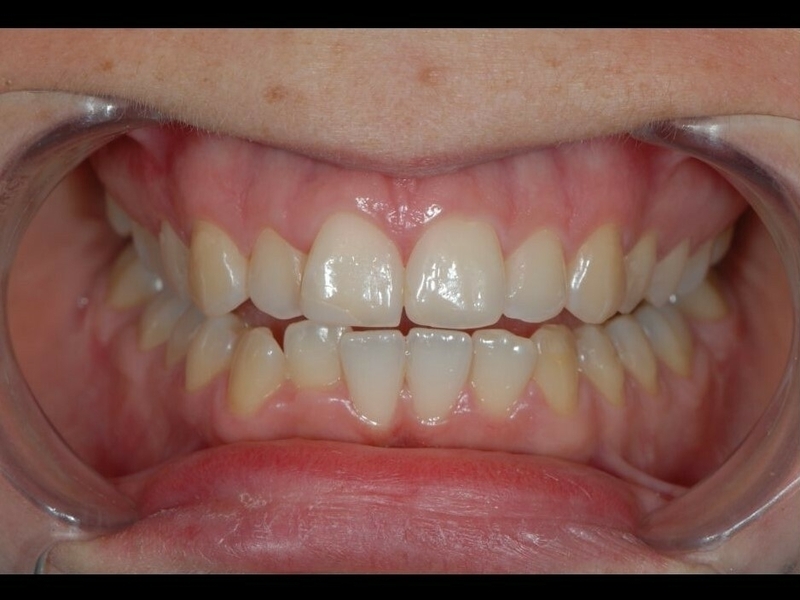

Cas 1 - Orthodontie par aligneurs invisibles

Après